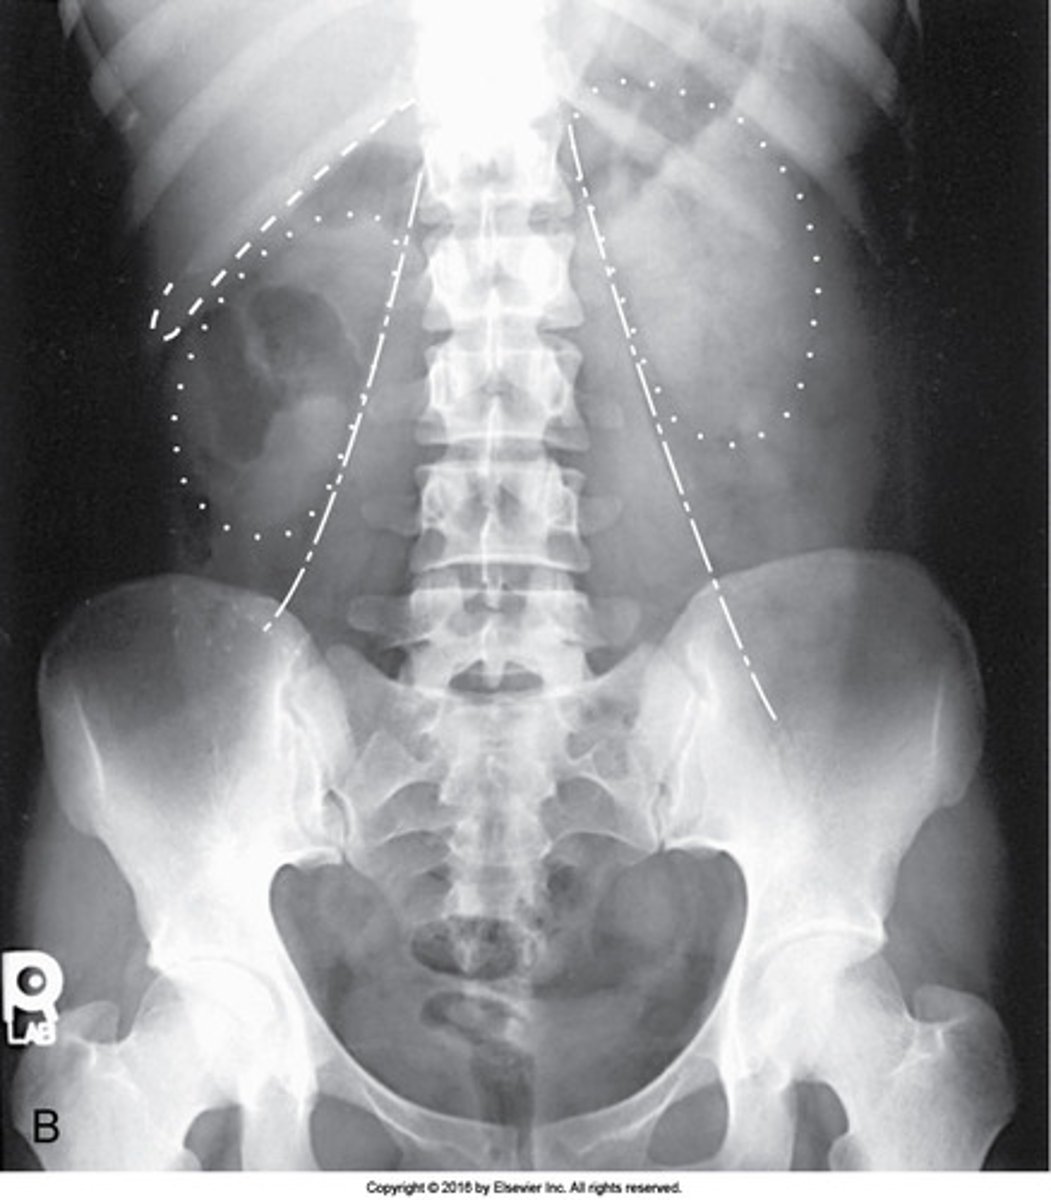

Which structures are outlined with dots in this AP image of the abdomen?

Kidneys